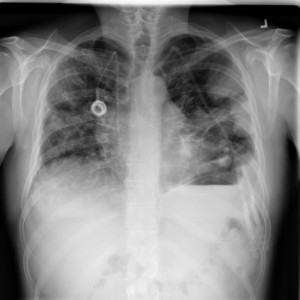

Anomaly detection is the problem of recognizing abnormal inputs based on the seen examples of normal data. Despite recent advances of deep learning in recognizing image anomalies, these methods still prove incapable of handling complex medical images, such as barely visible abnormalities in chest X-rays and metastases in lymph nodes. To address this problem, we introduce a new powerful method of image anomaly detection. It relies on the classical autoencoder approach with a re-designed training pipeline to handle high-resolution, complex images and a robust way of computing an image abnormality score. We revisit the very problem statement of fully unsupervised anomaly detection, where no abnormal examples at all are provided during the model setup. We propose to relax this unrealistic assumption by using a very small number of anomalies of confined variability merely to initiate the search of hyperparameters of the model. We evaluate our solution on natural image datasets with a known benchmark, as well as on two medical datasets containing radiology and digital pathology images. The proposed approach suggests a new strong baseline for image anomaly detection and outperforms state-of-the-art approaches in complex medical image analysis tasks.